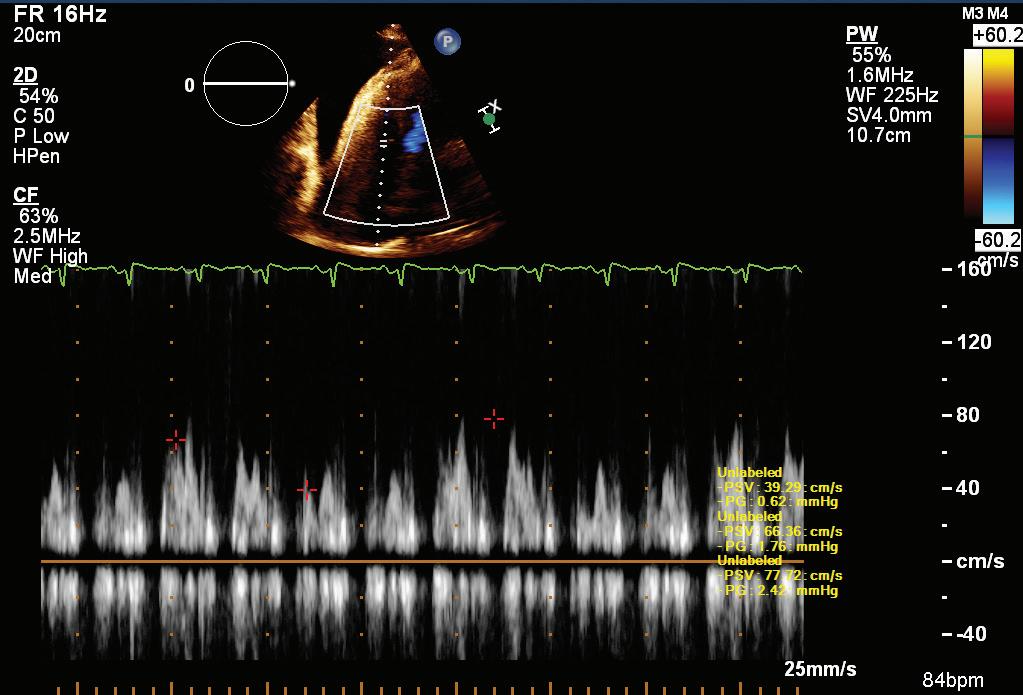

A 57-year-old man presented with a three-decade history of recurrent episodes of palpitation with alarming jugular venous pulsation, but without syncope. Each episode spontaneously reverted to the normal sinus rhythm 6–8 hours after the onset. Cardiac auscultation raised the suspicion of underlying rheumatic mitral stenosis. A 12-lead ECG was suggestive of a WPW pattern with a right posterior septal accessory pathway (Figure 1A). A chest X-ray in the posterior–anterior view was consistent with cardiac auscultation (Figure 1B). A transoesophageal echocardiogram confirmed rheumatic mitral stenosis (Figure 2A and Supplementary Material Video 1). The pliable mitral valve area was 0.8 cm2 and the mean gradient was 17 mmHg at a heart rate of 87 BPM. The coronary angiogram was normal.

On the day of the procedure, the first balloon mitral valvotomy was performed from a right femoral approach using a 23–26 mm Accura balloon (Vascular Concepts) after transeptal access using an 8 Fr SL-1 sheath and a BRK-0 needle (St Jude Medical). A transeptal puncture was performed after proper needle tip position was confirmed by fluoroscopy (right anterior oblique, left anterior oblique and 90° lateral views) and transoesophageal echocardiography (bicaval and short axis views; Figure 3A). The mean left atrial pressure prior to the valvotomy was 31 mmHg. The balloon was inflated to 26 mm in the right anterior oblique 20° position under fluoroscopy (Figure 3B) because the patient was 160 cm tall. The mitral valve area increased to 2.2 cm2 without any additional mitral regurgitation, and the mean left atrial pressure decreased to 12 mmHg without any mitral valve gradient. Immediate transthoracic echocardiography showed that the mitral valve gradient had decreased to 7/2 mmHg with negligible mitral regurgitation.